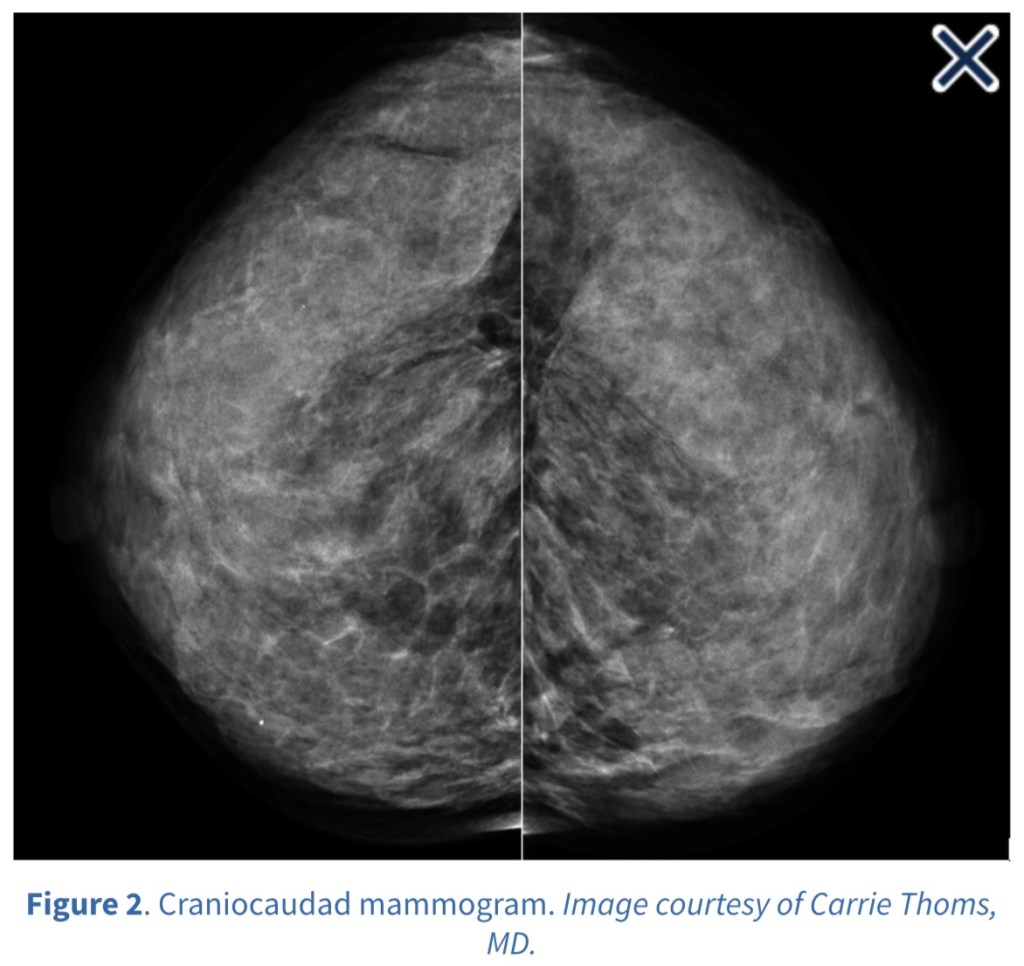

• It should include a diagnostic mammogram on the affected side and a screening mammogram on the nontreated side:

• Bilateral annual mammography is recommended thereafter